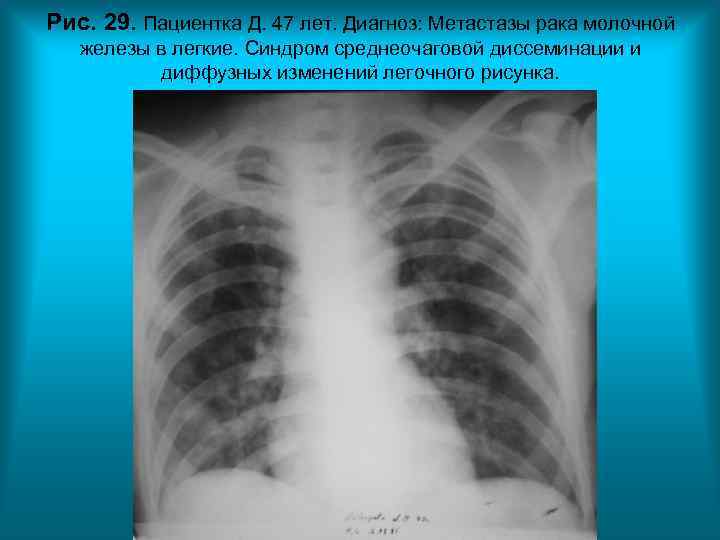

Рис. 29. Пациентка Д. 47 лет. Диагноз: Метастазы рака молочной железы в легкие. Синдром среднеочаговой диссеминации и диффузных изменений легочного рисунка. Н. С. Воротынцева. С. С. Гольев Рентгенопульмонология